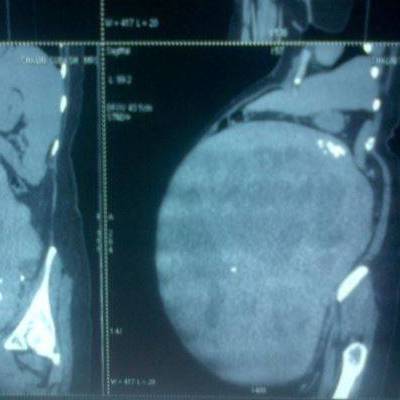

Tumor pesa 13 kg e possui 53 cm de diâmetro | Foto: Reprodução

Cirurgi?es operaram mulher de 52 anos por mais de tr?s horas. A paciente n?o tinha ideia de que havia um tumor gigante instalado no seu ventre. Ele foi considerado o maior tumor uterino do mundo, pesando 13 kg e medindo 53 cent?metros de di?metro.

Dr. Mani Mekalai, chefe do departamento do hospital de obstetr?cia e ginecologia, disse que a equipe estava "chocada" ao ver as imagens. "Pelo seu tamanho, o tumor poderia facilmente ter come?ado a crescer h? mais de 20 anos", afirma o m?dico. Latha foi levada para a sala de opera?es dois dias depois de ter sido internada.